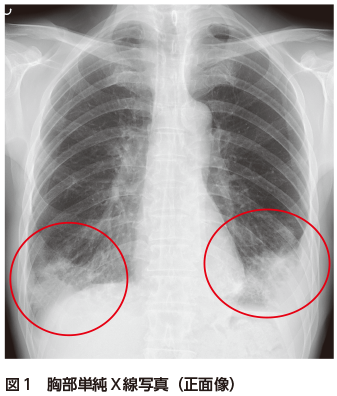

• A2:陰影分布が広範にもかかわらず明らかな発熱や炎症反応上昇を認めないことから,非感染性肺炎を考慮し胸部CTを追加する.

胸部単純X線写真では両下肺野に浸潤影を認める(図1).胸部CTでは両肺下葉の末梢気管支周囲に浸潤影およびすりガラス影の散在を認める(図2).肺底部は胸膜側優位に気管支透亮像を伴う広範な浸潤影を認める(図3).一部は非区域性に分布している(図3).